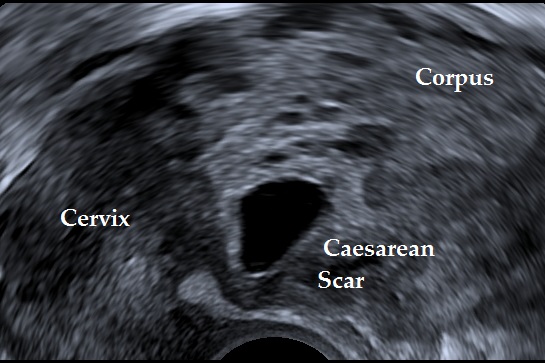

The following ultrasound criteria may be used for the diagnosis of caesarean scar ectopic pregnancy: Empty uterine cavity, gestational sac or solid mass of trophoblast located anteriorly at the level of the internal os embedded at the site of the previous lower uterine segment caesarean section scar, thin or absent layer of myometrium between the gestational sac and the bladder, evidence of prominent trophoblastic / placental circulation on Doppler examination and empty endocervical canal (Elson CJ et al., 2016).